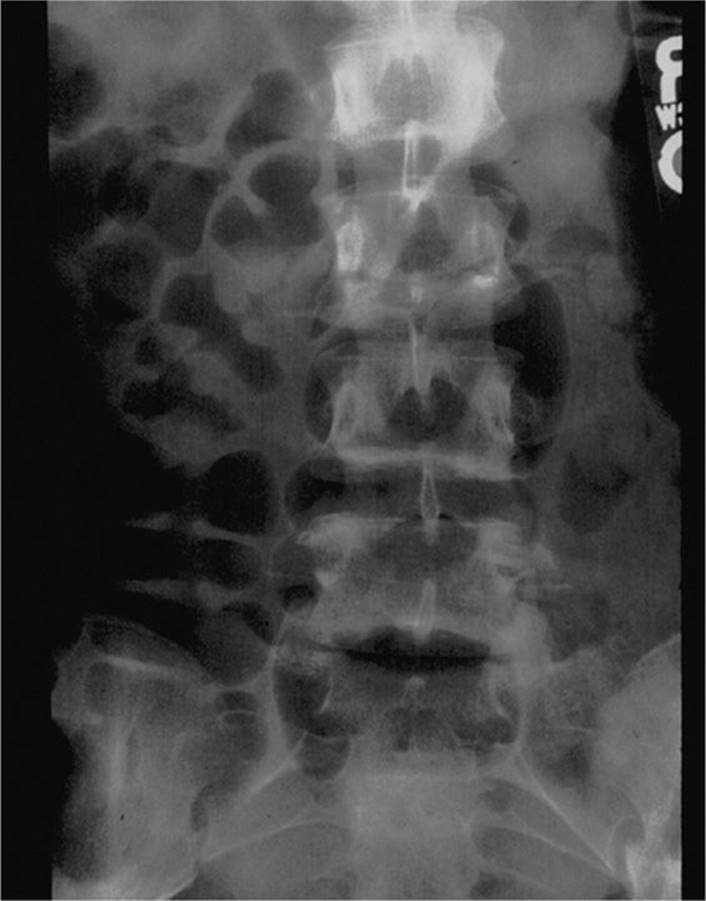

Multisystem trauma, along with abdominal injury, is common when an automobile strikes a child (Table 26-1). Waddell’s triad (Fig. 26-1) demonstrates a pattern of pediatric pedestrian injury with impact first to the upper leg, then chest and abdomen, followed by head. The head and extremity components of Waddell’s triad should not divert attention from intra-abdominal injury that may include life-threatening hemorrhage. In countries in which motorists drive on the right side of the road, the most common injuries are on the left side as children are often struck crossing the street, and frequently result in splenic injuries. The lap belt complex in the restrained child is characterized by ecchymosis, abrasion, or erythema in the pattern of a lap belt (seat belt sign) across the abdomen (Figs. 26-2 and 26-3) and flanks (Grey–Turner sign) and occurs in up to 10% of restrained children. The injury is thought to occur because of an improperly applied restraint that allows the lap belt to ride up and compress the abdomen as the child slides forward under the belt. Presence of the “seat belt sign” always warrants further evaluation and has been associated with increased risk of gastrointestinal injury.4,5

FIGURE 26-3. Chance fracture of the lumbar spine. Because of improperly applied lap belt which rides up and compresses the child’s abdomen during a motor vehicle collision. (Used with permission from Dr. James F. Holmes, Department of Emergency Medicine, University of California, Davis Medical Center.)